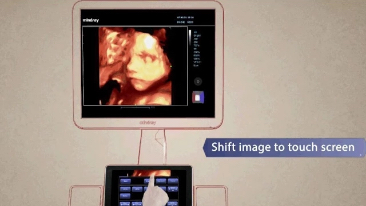

MedSight

DC-60 lets you transfer clinical images and cine to your IOS or android powered smart device via an interactive app. It could be for a to-be-mother wanting to share the images of the fetus with her family or friends. It could be a training session or a discussion with your peers on a rare case. You can now take the clinical examinations with you wherever needed with MedSight.